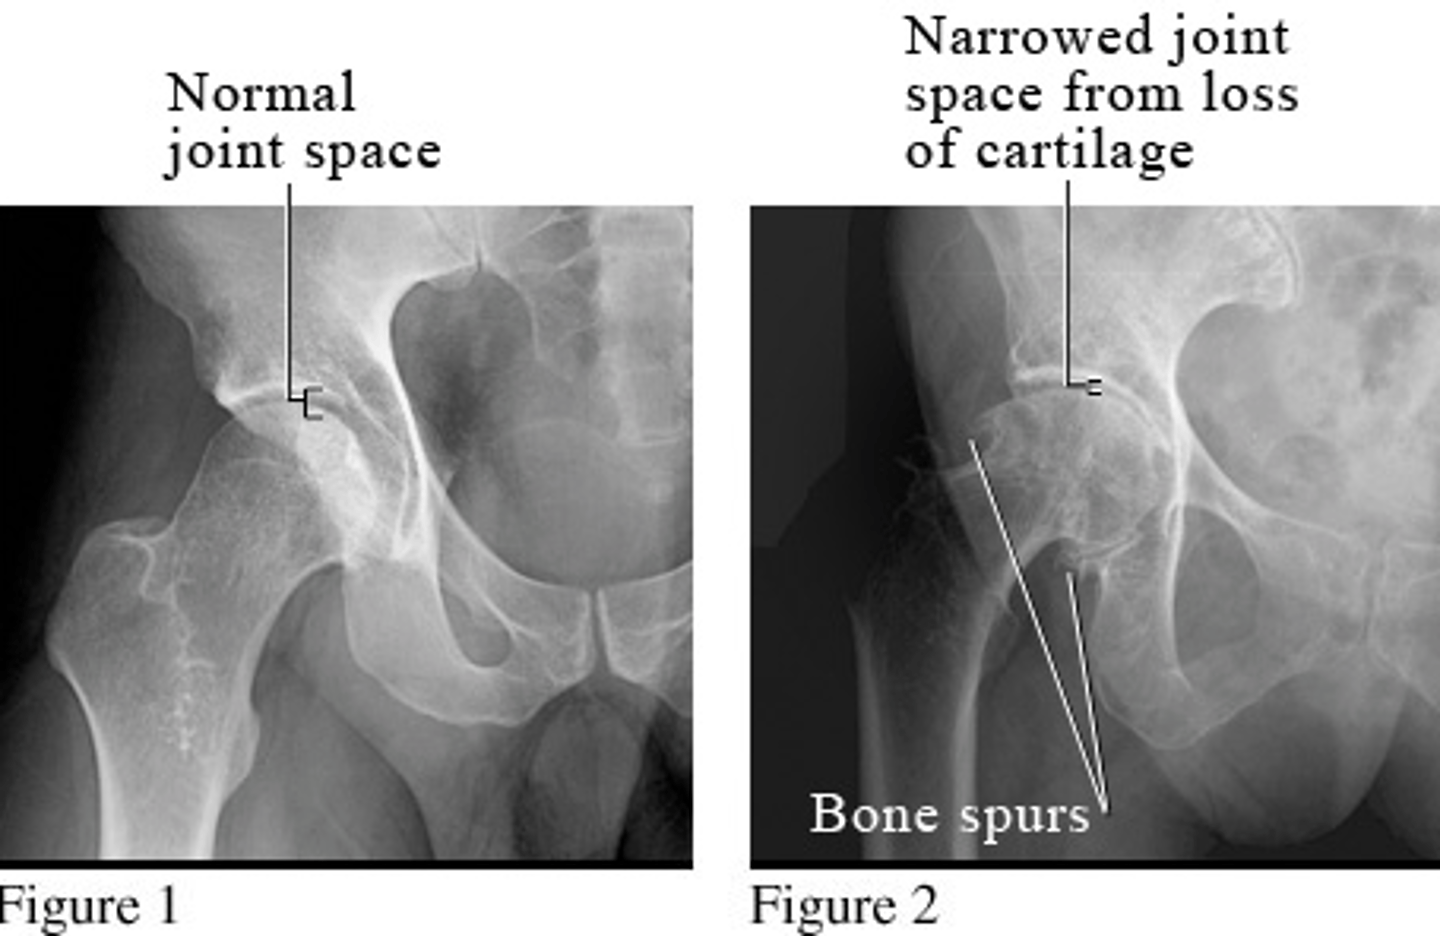

osteoarthritis

wear and tear arthritis

*occurs equally in males and females

**associated with trauma (50%) or idiopathic (50%)

***increased with height to weight ratio

STRUCTURES--> joints, primarily weight-bearing

FUNCTIONAL DEFICITS--> decreased ROM, pain

COMPENSATORY MOVEMENTS--> antalgic gait pattern, may present with Trendelenberg gait due to muscle weakness, or may see gluteus medius gait

*associated with a high percentage of total hip replacement